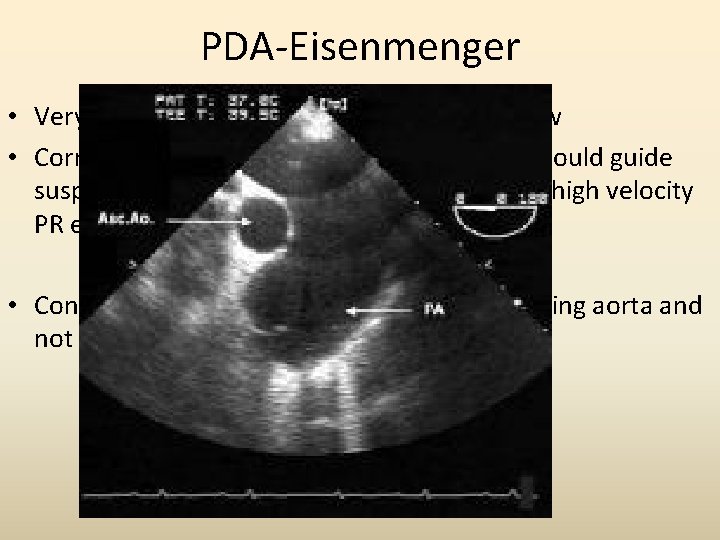

PDA-Eisenmenger • Very difficult to demonstrate the Doppler flow • Corroborative evidence and clinical picture should guide suspicion : Septal flattening, RVH, dilated PA, high velocity PR etc • Contrast Echo : reveal bubbles in the descending aorta and not in the ascending aorta